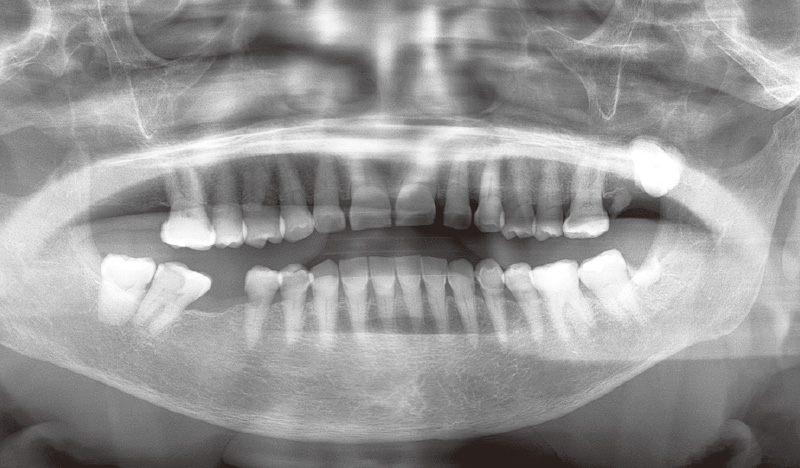

金属アレルギーを発症され、メタルインレーをセラミックに変更する治療を行っている【症例2】の患者さんのように、同じような処置が続く場合も「ルナビューショット」は有用です。初回治療時の動画を見せながら、どんな治療を行い、結果がどうなるのか、現在どういう状態にあるのかを説明し、患者さんに状況の理解を促します。そうすれば、次回以降の説明もスムーズになりますし、特にこの患者さんのように治療が長期にわたる場合、変化がわかりづらいと精神的に疲れてしまうこともあります。そのため、治療経過(変化)をお見せすることは、治療のモチベーションを維持・向上させるためにも必要なことだと思っています。

患者説明に用いる「TrinityCore3」は、クリック一つで口腔内写真やパノラマX線など、すべての画像データを素早く呼び出し、時系列順に一覧表示することもできます。日々の診療の振り返りや説明用画像への加工も簡単な操作で行えますし、一覧を見ることで患者さんの名前と検査データ、口腔内の情報が即座に一致し、説明がよりスムーズに進められるというメリットもあります。また、すべての情報を一元管理できればこの先患者さんが増えても安心ですし、万が一治療中に何らかのトラブルが発生した場合にも検証材料として役立つことでしょう。さらに今後多くの症例が集まれば、院内での研修や勉強会にも活用できると期待しています。